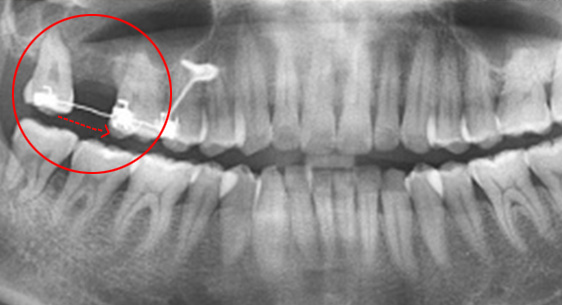

이가 고르지 않고 입술이 나와 보여 개선되기를 원하심. 일반적인 교정치료 방법인 위/아래 작은 어금니 발치 후 앞니 견인을 계획하였으며,

좌측 아래쪽에는 상실된 어금니를 대체하고 있던 임플란트의 뿌리와 지대주 부분만 남아있어 가급적 자연치 보존을 위해 작은

어금니 대신 임플란트를 제거하고 사랑니를 포함한 어금니를 전방으로 당겨오는 치료 진행.